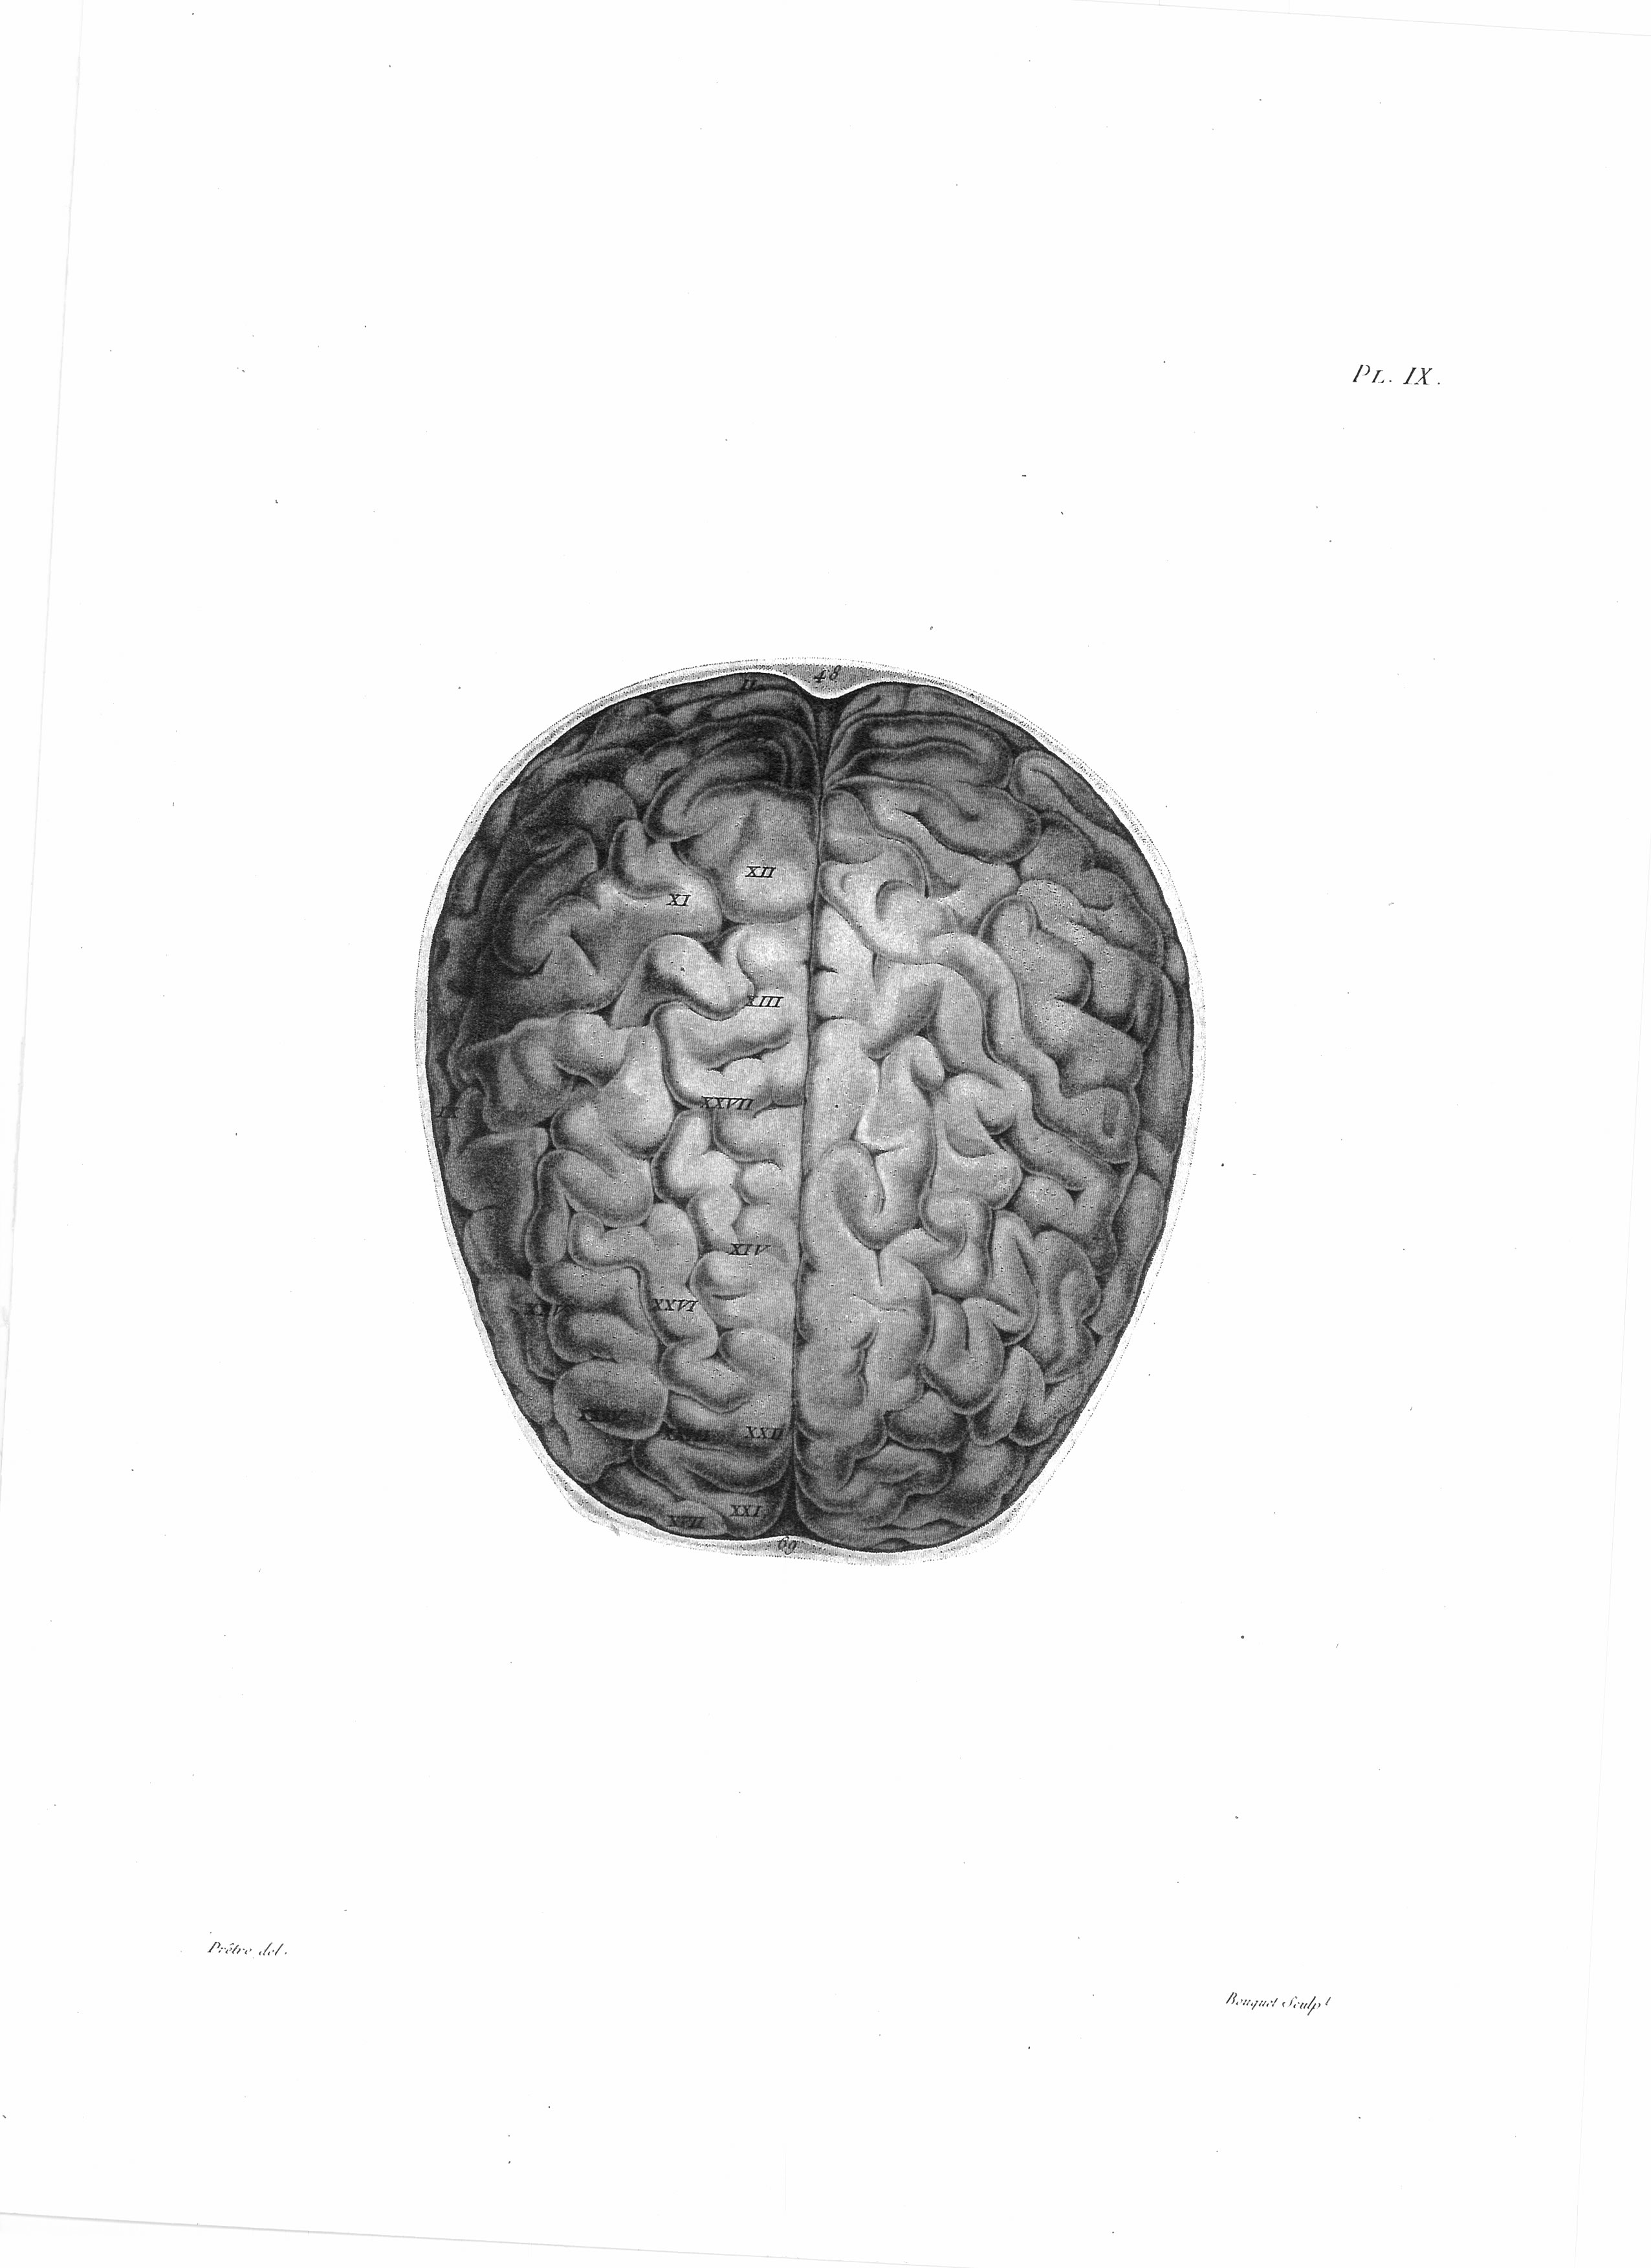

Gall, F. J. (1818). Anatomie et physiologie du système nerveux en général, et du cerveau en particulier, Avec des observations sur la possibilité de reconnoître plusieurs dispositions intellectuelles et morales de l´homme et des animaux, par la configuration de leurs têtes.

Librairie Grecque-Latine-Allemande, Vol. 3, I-XXXV u. 1-379 100 planches.